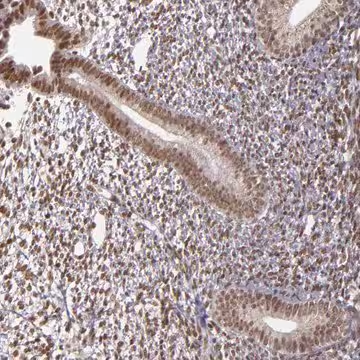

Anti-ZFX antibody produced in rabbit, 1 X 100 µL (HPA001748-100UL)